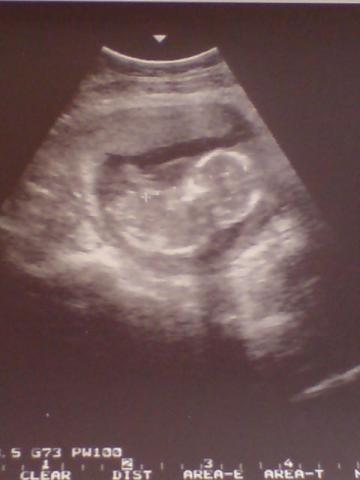

ime a legutobbi uh foto Miniröl, es a ´mellesleges´problemam... :shock: